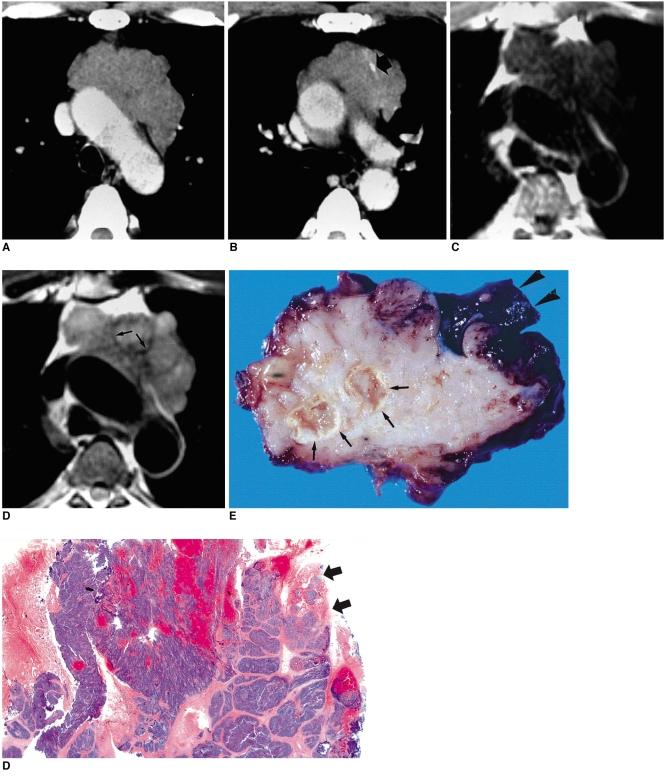

Thymic epithelial tumor is a distinctive pathologic entity exhibiting variable histologic features and heterogeneous oncologic behavior. Among the various classification systems, that of the World Health Organization has been adopted because of good correlation between histologic appearance and oncologic behavior. Radiologically, a smooth contour and round shape are most suggestive of a type-A tumor, whereas an irregular contour most strongly suggests type C. Pleural seeding is rare in type-A and AB tumors; calcification is suggestive of type B. Type-C tumors are significantly larger and more commonly associated with lymphadenopathy than type B3. At T2-weighted MR imaging, lobular internal architecture is more prominent in types B1, B2, and B3 tumors than in others. However, imaging findings among the various types overlap to some extent, and the ability of imaging studies to differentiate types AB, B1, B2, and B3 is limited.